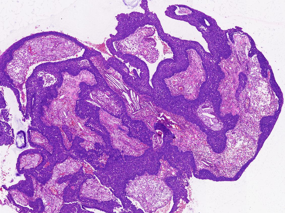

病理特征:宽薄乳头、 迷宫样内翻生长、单一肿瘤细胞形态、棘层松解、显著中性粒细胞浸润;

可见:细胞旋涡、透明细胞变、微囊形成、黏液纤毛上皮帽、部分肿瘤细胞异型性增加、坏死。

具有纤毛上皮帽

1、内翻性乳头状瘤:乳头结构简单、圆形,巢中央常形成囊腔,细胞成分复杂,包括鳞状细胞、纤毛柱状细胞和杯状细胞,可通过分子检测及AFF2 免疫组化鉴别。